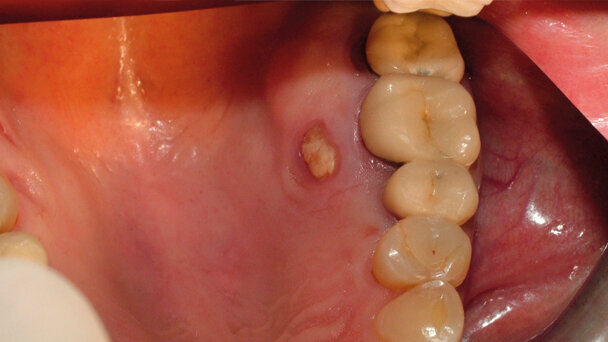

La BRONJ (Bisphosphonate-Related OsteoNecrosis of the Jaws) è definita come un’area di osso esposto nella regione maxillo-facciale che non guarisce dopo 8 settimane, in pazienti che non sono stati sottoposti a radioterapia del distretto testa-collo e che sono stati in terapia con bifosfonati1. Recentemente, il termine BRONJ è stato sostituito con il termine MRONJ (Medication-Related OsteoNecrosis of the Jaw) che è stato introdotto dall’Associazione americana dei chirurghi orali e maxillo-facciali a seguito del costante aumento di casi di necrosi mascellari e mandibolari associati a terapia con farmaci antiriassorbimento e antiangiogenetici.

Dal 2003 sono iniziati ad emergere casi di necrosi associati all’utilizzo di bifosfonati per via endovenosa, principalmente nei pazienti oncologici2. Tuttavia, molte pubblicazioni scientifiche hanno anche riportato dei casi di necrosi associati ai bifosfonati assunti per via orale utilizzati per il trattamento dell’osteoporosi e del morbo di Paget3-5. Per quanto riguarda l’alendronato, utilizzato dall’88% dei pazienti con osteoporosi, l’incidenza di MRONJ è circa di 0,7 casi per 100.000 pazienti l’anno6,7. Il relativo basso rischio di MRONJ nei pazienti con osteoporosi in terapia con bifosfonati orali può essere dovuto alla dose e alla frequenza di somministrazione del farmaco8. La maggioranza dei casi di MRONJ riportati in letteratura si è verificata dopo estrazioni dentarie o interventi di chirurgia ossea (69% dei casi)9,10.

Tuttavia, alcune MRONJ sembrano verificarsi spontaneamente (senza apparenti traumi) in alcuni pazienti in terapia con questi farmaci11. In letteratura sono state descritte necrosi spontanee sul palato e nel torus mandibolare12. Nel 2007 è stato pubblicato un caso di MRONJ che è stato risolto solamente con terapia topica e sistemica13. Mentre nel 2008, Engroff e Coletti14 hanno descritto un caso di MRONJ del palato trattato con debridement chirurgico e con innesto tessutale.